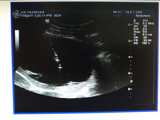

近日,我院成功完成了首例超声引导下经皮穿刺肾盂造瘘术以及首例巨大脾囊肿穿刺置管引流+硬化术,这标志着我院在超声新技术的开展方面又取得了新的突破。 77岁的徐老伯,因膀胱肿瘤压迫导致尿路梗阻、双肾重度积水,慢性肾衰。这类患者原则上首先选择膀胱镜下逆行插管引流。但徐老伯肿瘤大且易出血,无法进行逆行插管,我...2017-11-24